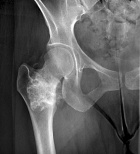

Patient is a 34 y/o female who presents after a hysterosalpingogram revealed a R. femoral lesion

Patient does state a hx. of mild activity related R. hip pain; PMH: unremarkable

PE: no palpable mass or TTP over R. prox. thigh; full PROM hip w/ no tenderness; NVI

Zoom image: Radiological image Radiological image.